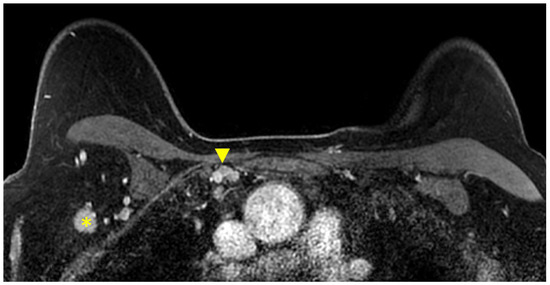

3.1.6. Evaluation of Internal Mammary Lymph Nodes (IMLNs)

3.2. The Impact of MRI on Decisions for Breast Conservation Therapy